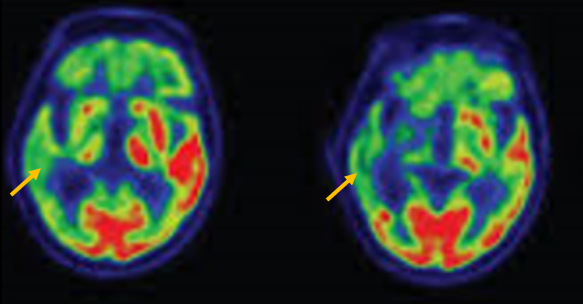

피질 기저핵 변성은 비대칭 증상을 두드러지게 보인다는 점에서 파킨슨병과 비슷합니다. 그러나 파킨슨병과 비교해 보았을 때 양측의 차이가 아주 심하게 나타난다는 특징이 있습니다. 질병 초기에 한쪽 손으로 동작을 하거나 계획된 행동을 하는 기능이 현저하게 떨어집니다. 간단한 손가락 모양도 따라 하지 못하는 현상을 보입니다. 또한 의지와 상관없이 제멋대로 움직이는 통제불능 손이 나타날 수 있습니다. 체위 떨림, 경축, 운동 완만과 같은 파킨슨병에서 볼 수 있는 증상들은 피질 기저핵 변성에서도 관찰될 수 있습니다. 또한 집중력 장애, 수행 장애, 이름 대기나 언어의 유창성이 떨어지는 등 전두엽 및 두정엽과 관련된 인지 장애가 나타납니다. 피질 기저핵 변성은 뇌 자기공명영상(MRI)에서 증상의 반대쪽 전두두정엽의 위축 소견이 특징적으로 나타납니다. 뇌포도당 양전자 단층촬영(PET)에서도 전두엽, 뇌기저핵에 비대칭적인 대사 저하의 소견이 보입니다.

[피질기저핵 변성 환자의 뇌포도당 양전자 단층촬영에서 확인되는 비대칭적인 대사 기능 저하]